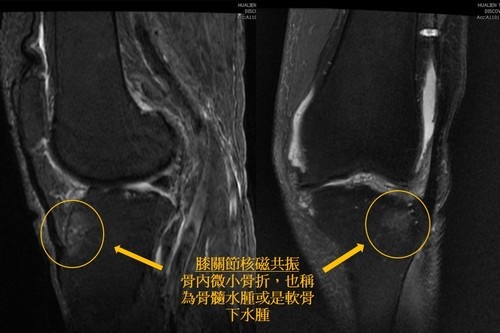

今年一月詹女士膝蓋積水嚴重,抽出左膝的積水後疼痛雖然有改善,但是過一陣子又繼續發炎疼痛,王柏凱主任表示,這樣的膝關節疼痛不算少見,她屬於一般的膝蓋退化,且軟骨也都還在,並沒有到達需要換人工關節的程度,關節穩定性也不差,所以進一步為詹女士安排詳細的核磁共振檢查,發現脛骨(小腿骨)靠近膝關節的地方有骨頭內的微小骨折,一般X光是看不出來,也無法針對微小骨折作手術固定復位,多半只能被動休息、穿戴護具以及疼痛時吃止痛藥物,等待骨頭自行修復,一般需要數週時間才可能會修復,甚至可能超過一年以上也無法修復。